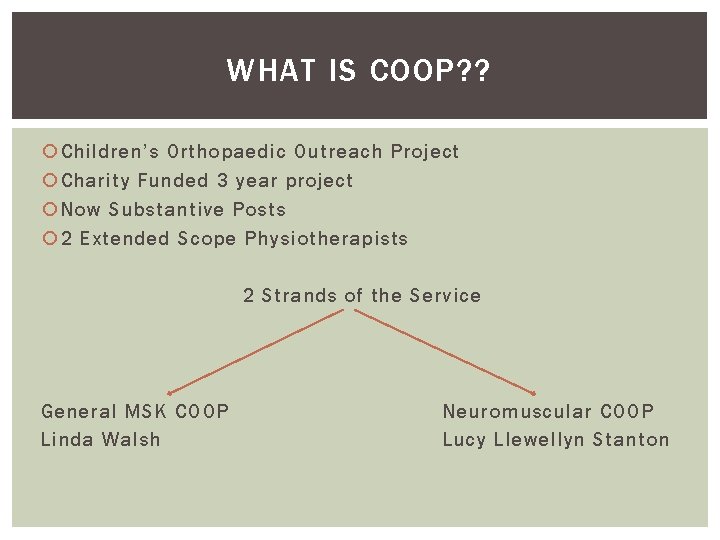

WHAT IS COOP? ? Children’s Orthopaedic Outreach Project Charity Funded 3 year project Now Substantive Posts 2 Extended Scope Physiotherapists 2 Strands of the Service General MSK COOP Linda Walsh Neuromuscular COOP Lucy Llewellyn Stanton